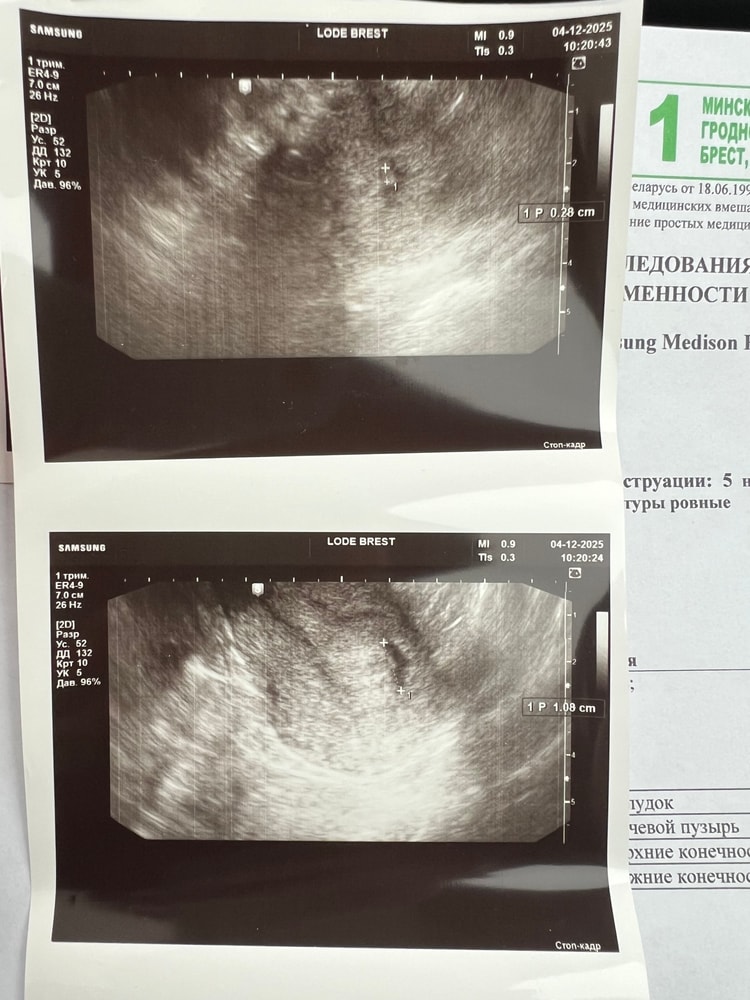

Наше первое узи 💕 Пока не видно эмбриона , только плодное яйцо и желточный мешочек.

по размерам сказали все вроде ок , прийти через неделю посмотреть растет ли маковка ☺️